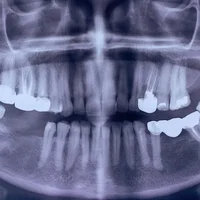

Défauts osseux autour des dents

Bouche et dents